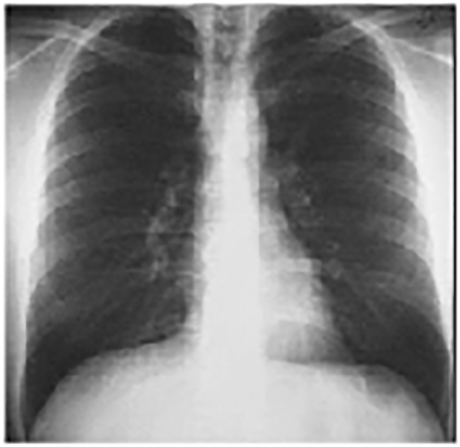

Another Patient's PA Chest X ray

For teaching purposes, the following PA chest X ray from another patient is presented.

This PA chest X ray is normal. It demonstrates no abnormalities of the bone structures, lung fields or cardiac silhouette. The right and left heart borders are normal as are the great vessels superior to the cardiac silhouette. Note the cardiothoracic ratio is also normal.